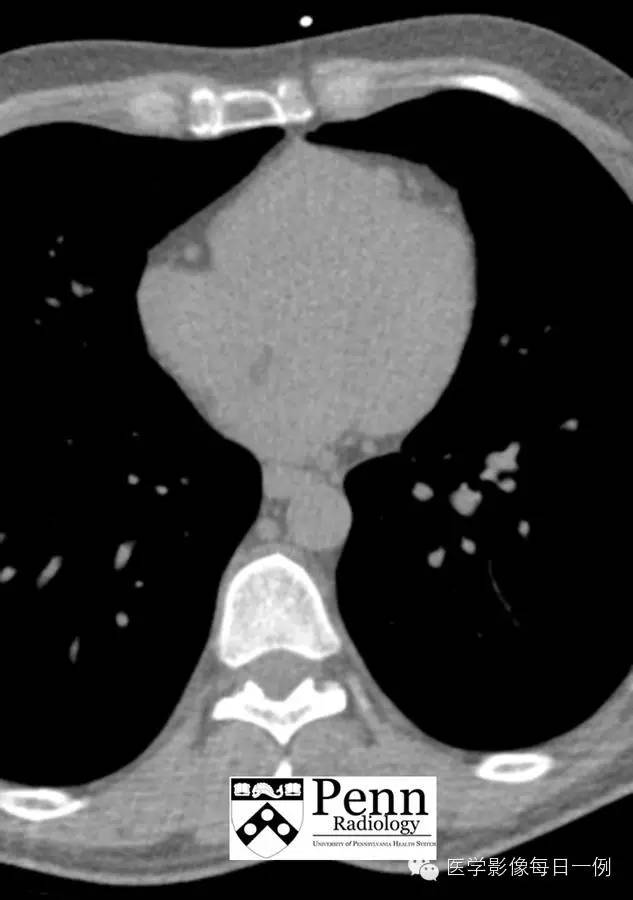

【病史】58岁男性,左侧胸痛。

ECG-gated CT images

Coronary CT image

A CT image ofthe left anterior descending (LAD) coronary artery is shown below.

注释:前降支可见重度狭窄,但位于第一对角支近侧,故为前降支近段,而非中段。狭窄为重度,接近95%。

【诊断】Critical coronary artery (LAD) stenosis 前降支重度狭窄

【影像学特征】

Chest x-ray:除重度狭窄外一般显示正常,晚期心力衰竭时可见心脏扩大及肺水肿。

Coronary CT: